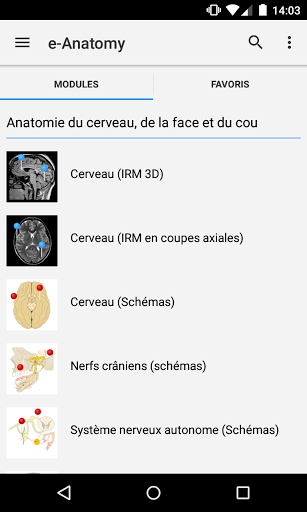

IMAIOS e-Anatomy adalah atlas anatomi manusia untuk dokter, ahli radiologi, mahasiswa kedokteran, dan teknisi radiologi. Dapatkan cuplikan lebih dari 26.000 gambar medis dan anatomi secara gratis sebelum berlangganan atlas anatomi manusia terperinci kami.

e-Anatomy didasarkan pada atlas daring IMAIOS e-Anatomy yang telah memenangkan penghargaan. Bawalah referensi anatomi manusia terlengkap, ke mana pun Anda pergi, di perangkat seluler atau tablet Anda.

e-Anatomy memiliki lebih dari 26.000 gambar yang berisi serangkaian gambar dalam tampilan aksial, koronal, dan sagital serta radiografi, angiografi, gambar diseksi, bagan anatomi, dan ilustrasi. Semua gambar medis diberi label dengan cermat, lebih dari 967.000 label tersedia dalam 12 bahasa termasuk Terminologia Anatomica Latin.

Fitur:

- Pilih label anatomi berdasarkan kategori